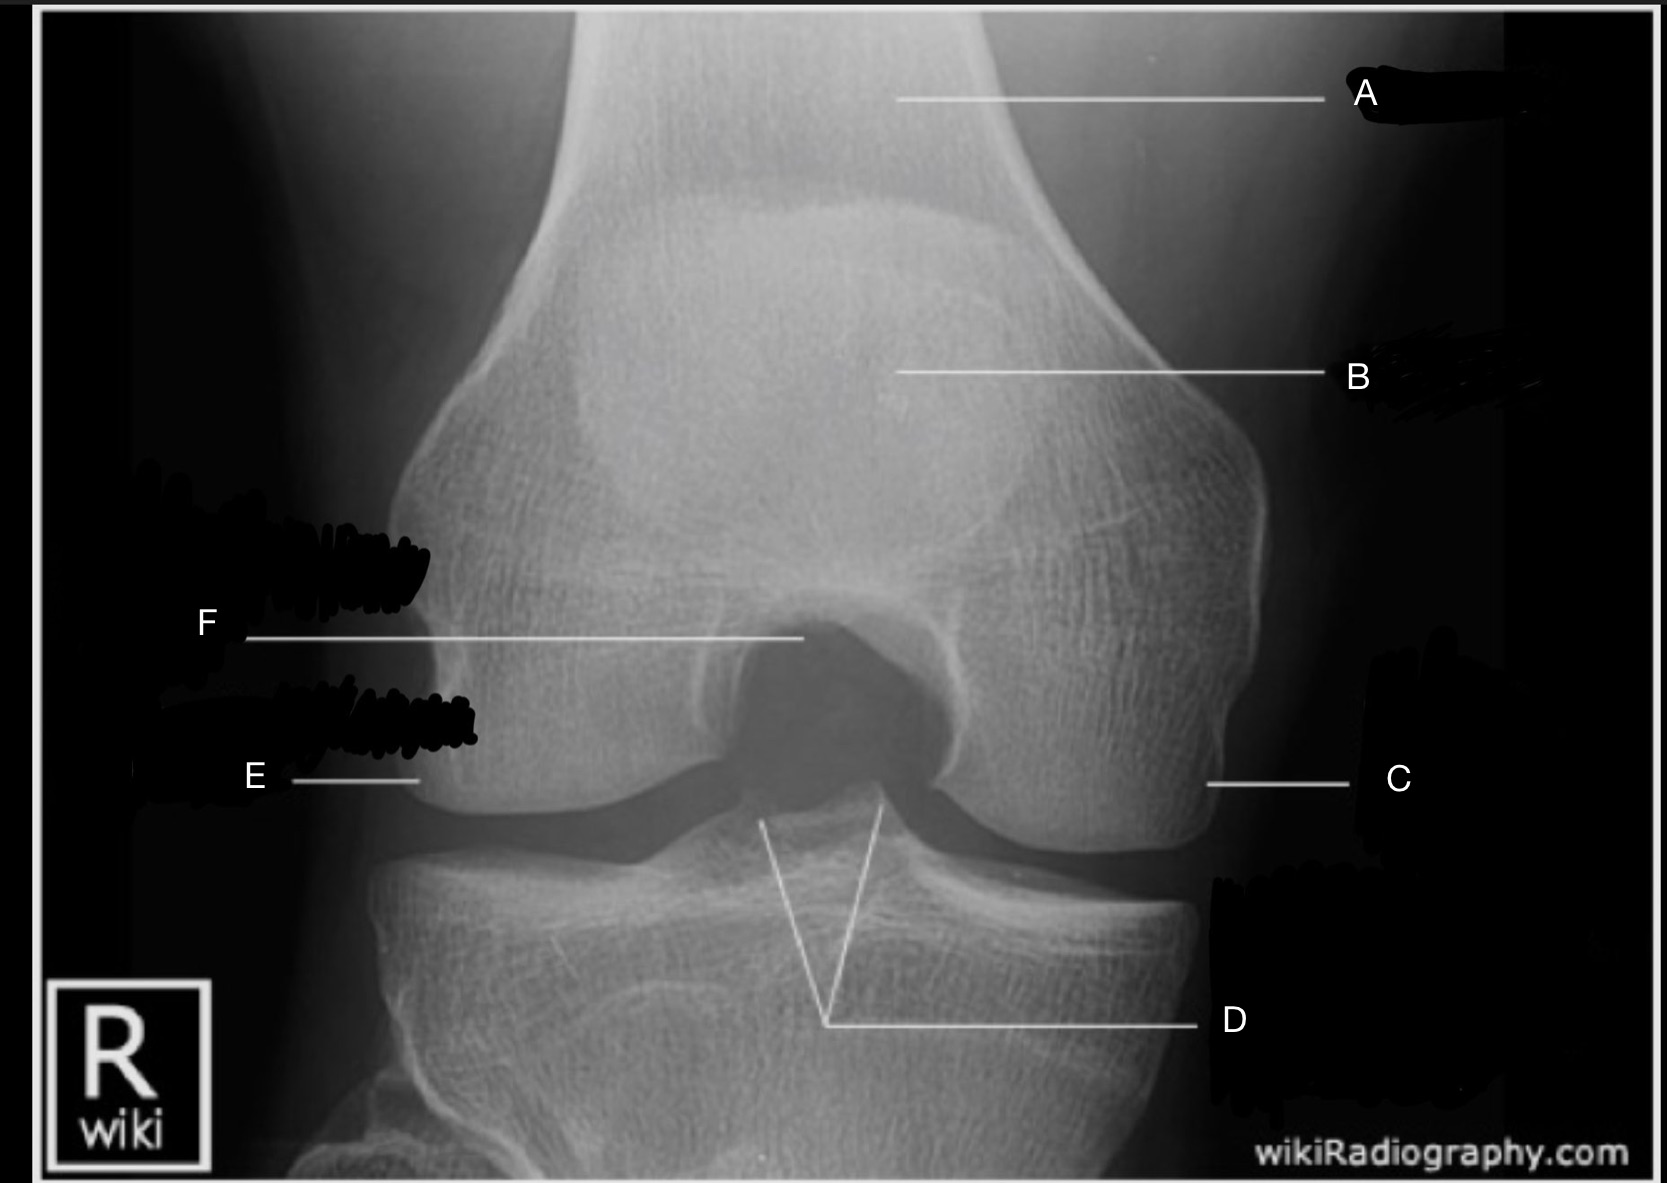

Name the projection.

Should it be repeated, if so why?

AP Knee

No

Label the image

A) Femur

B) Patella

C) Lateral femoral epicondyle

D) Intercondylar fossa

E) Intercondylar eminence

F) Femorotibial joint

G) Fibula

H) Tibia

I) Tibial condylar margin

J) Medial femoral epicondyle